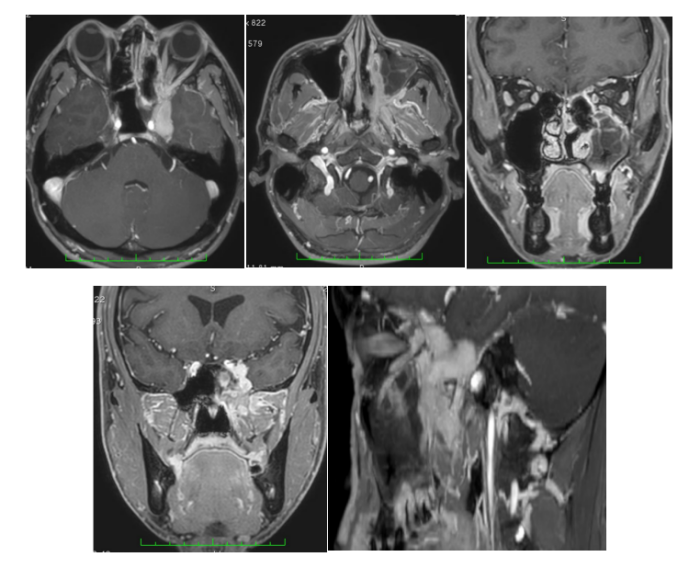

术前术后MRI对比

·术后10天进行了术后头颅磁共振检查。该扫描显示:无并发症,90%以上的整个实体肿瘤块的扩大切除,沿三叉神经分支和背侧海绵窦的小残留。